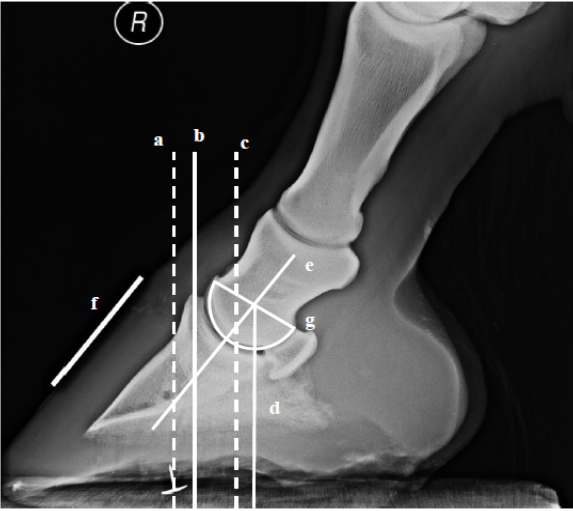

Radiographic analysis added another layer of insight. The external measure of the centre of rotation (CoR) corresponded closely with the internal centre of rotation of the distal interphalangeal joint, reinforcing its usefulness as a trimming landmark.

By contrast, the centre of pressure (CoP) did not align with the extensor process of the distal phalanx. This suggests that while some external markers are valid reflections of internal anatomy, others may be less reliable (Figure 3).

Figure 3. Radiographic validation of hoof landmarks. CoR correlated well with the distal phalanx, while CoP did not align with the extensor process.